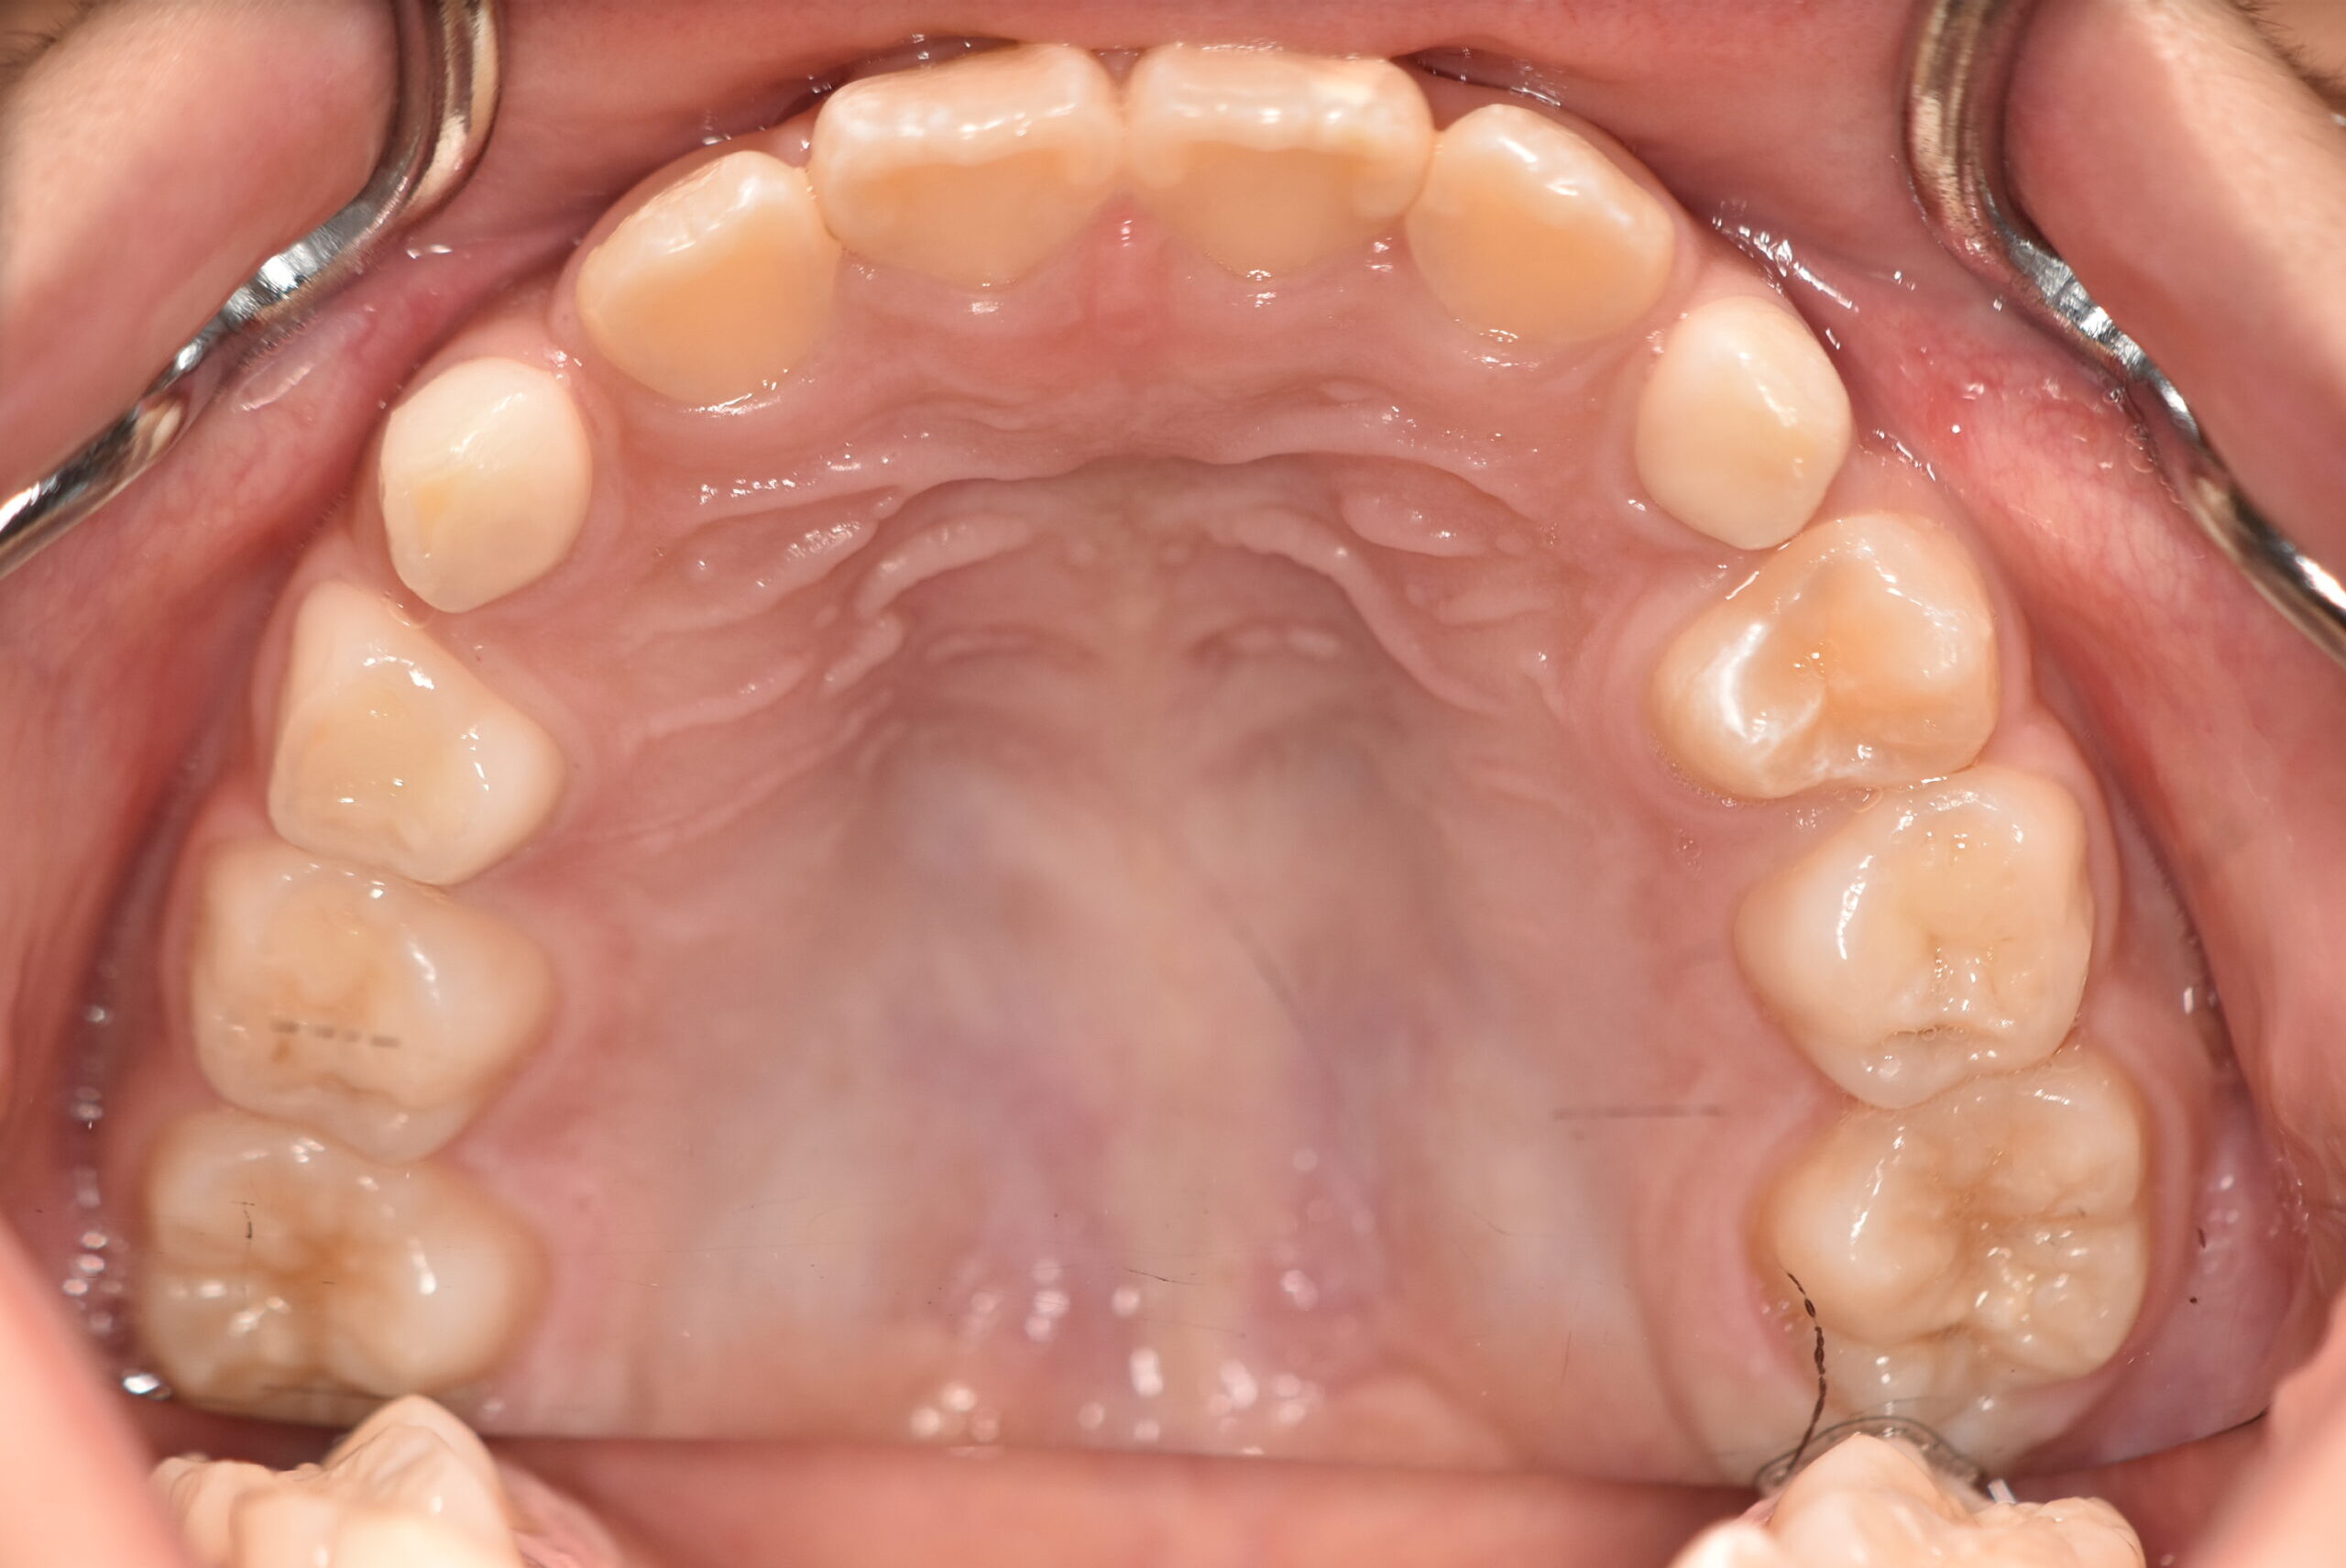

インビザラインファースト 【2724】

初診時

症例 症例 症例 症例

年齢

8歳 性 別 女性

治療期間 6ヶ月 費 用 矯正施術料:800,000円

調整料:4,000円/月

治療内容の詳細 初診時8歳の女児で、正中のズレを気にされ来院されました。

検査の結果、臼歯部交叉咬合を伴うアングルⅠ級不正咬合と診断しました。

治療としてはマウスピース矯正(インビザラインファースト)で配列を行い、上顎の側方拡大と萌出スペースを確保しました。

治療期間は、6ヶ月でした。

今後、側方歯生え変わりまで経過観察を行います。